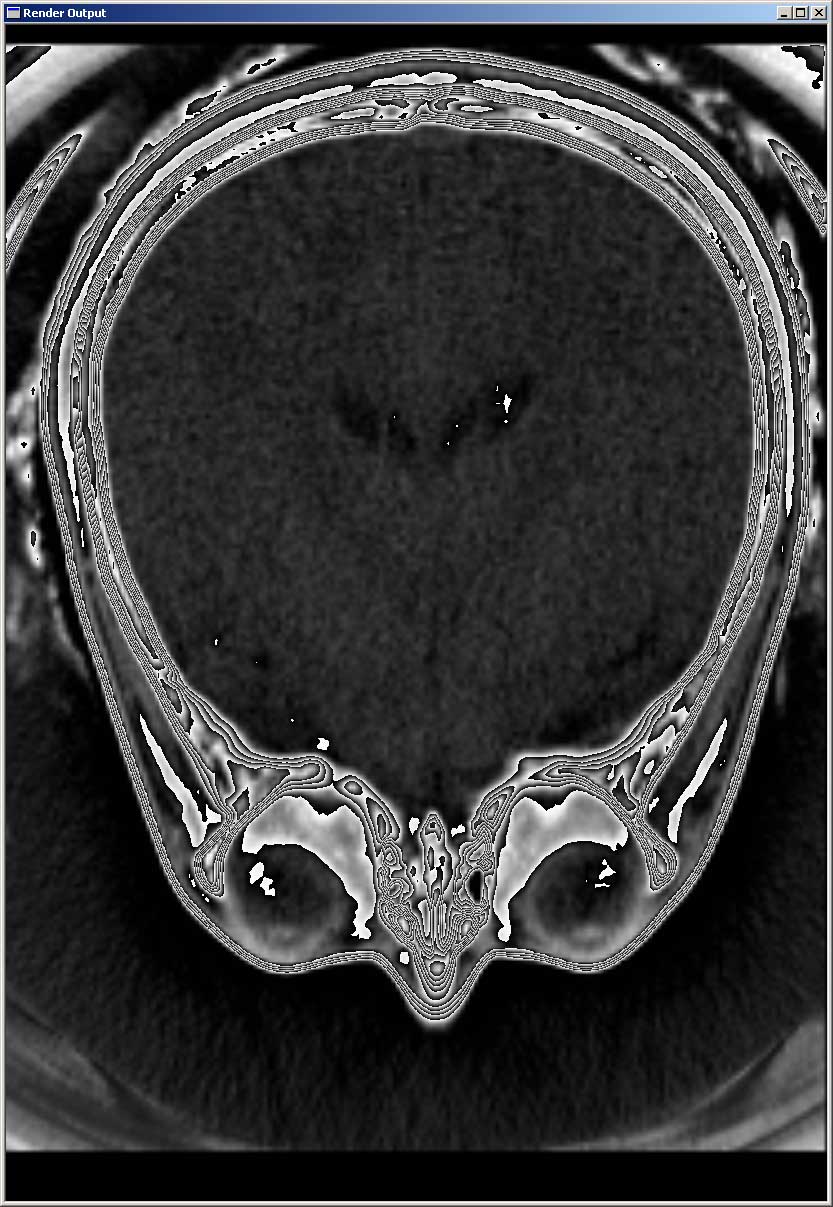

Slicing mit Transfer-Funktion (2)

Wir haben unserem Programm eine spezielle Transferfunktion beigefügt (diese kann aus der Datei "fullMappingRepeatingGradient.trf" geladen werden), die die besondere Eigenschaft hat, dass jedem 12-Bit Intisitäts-Wert lokal ein anderer 8-Bit Graustufenwert zugeordnet wird, ohne dass dabei Information verloren geht. Dadurch können auch feinste Unterschiede, wie hier z.B. die Gehirnstruktur deutlich wahrgenommen werden.